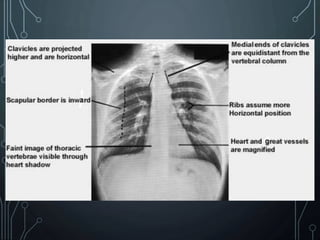

 Clavicles are projected higher and the ribs assume a

more horizontal position.

 The heart and great vessels appear magnified.

 A faint image of the ribs and thoracic vertebrae should

be visible through the heart shadow

 The outline of the heart and diaphragm should be

sharp.